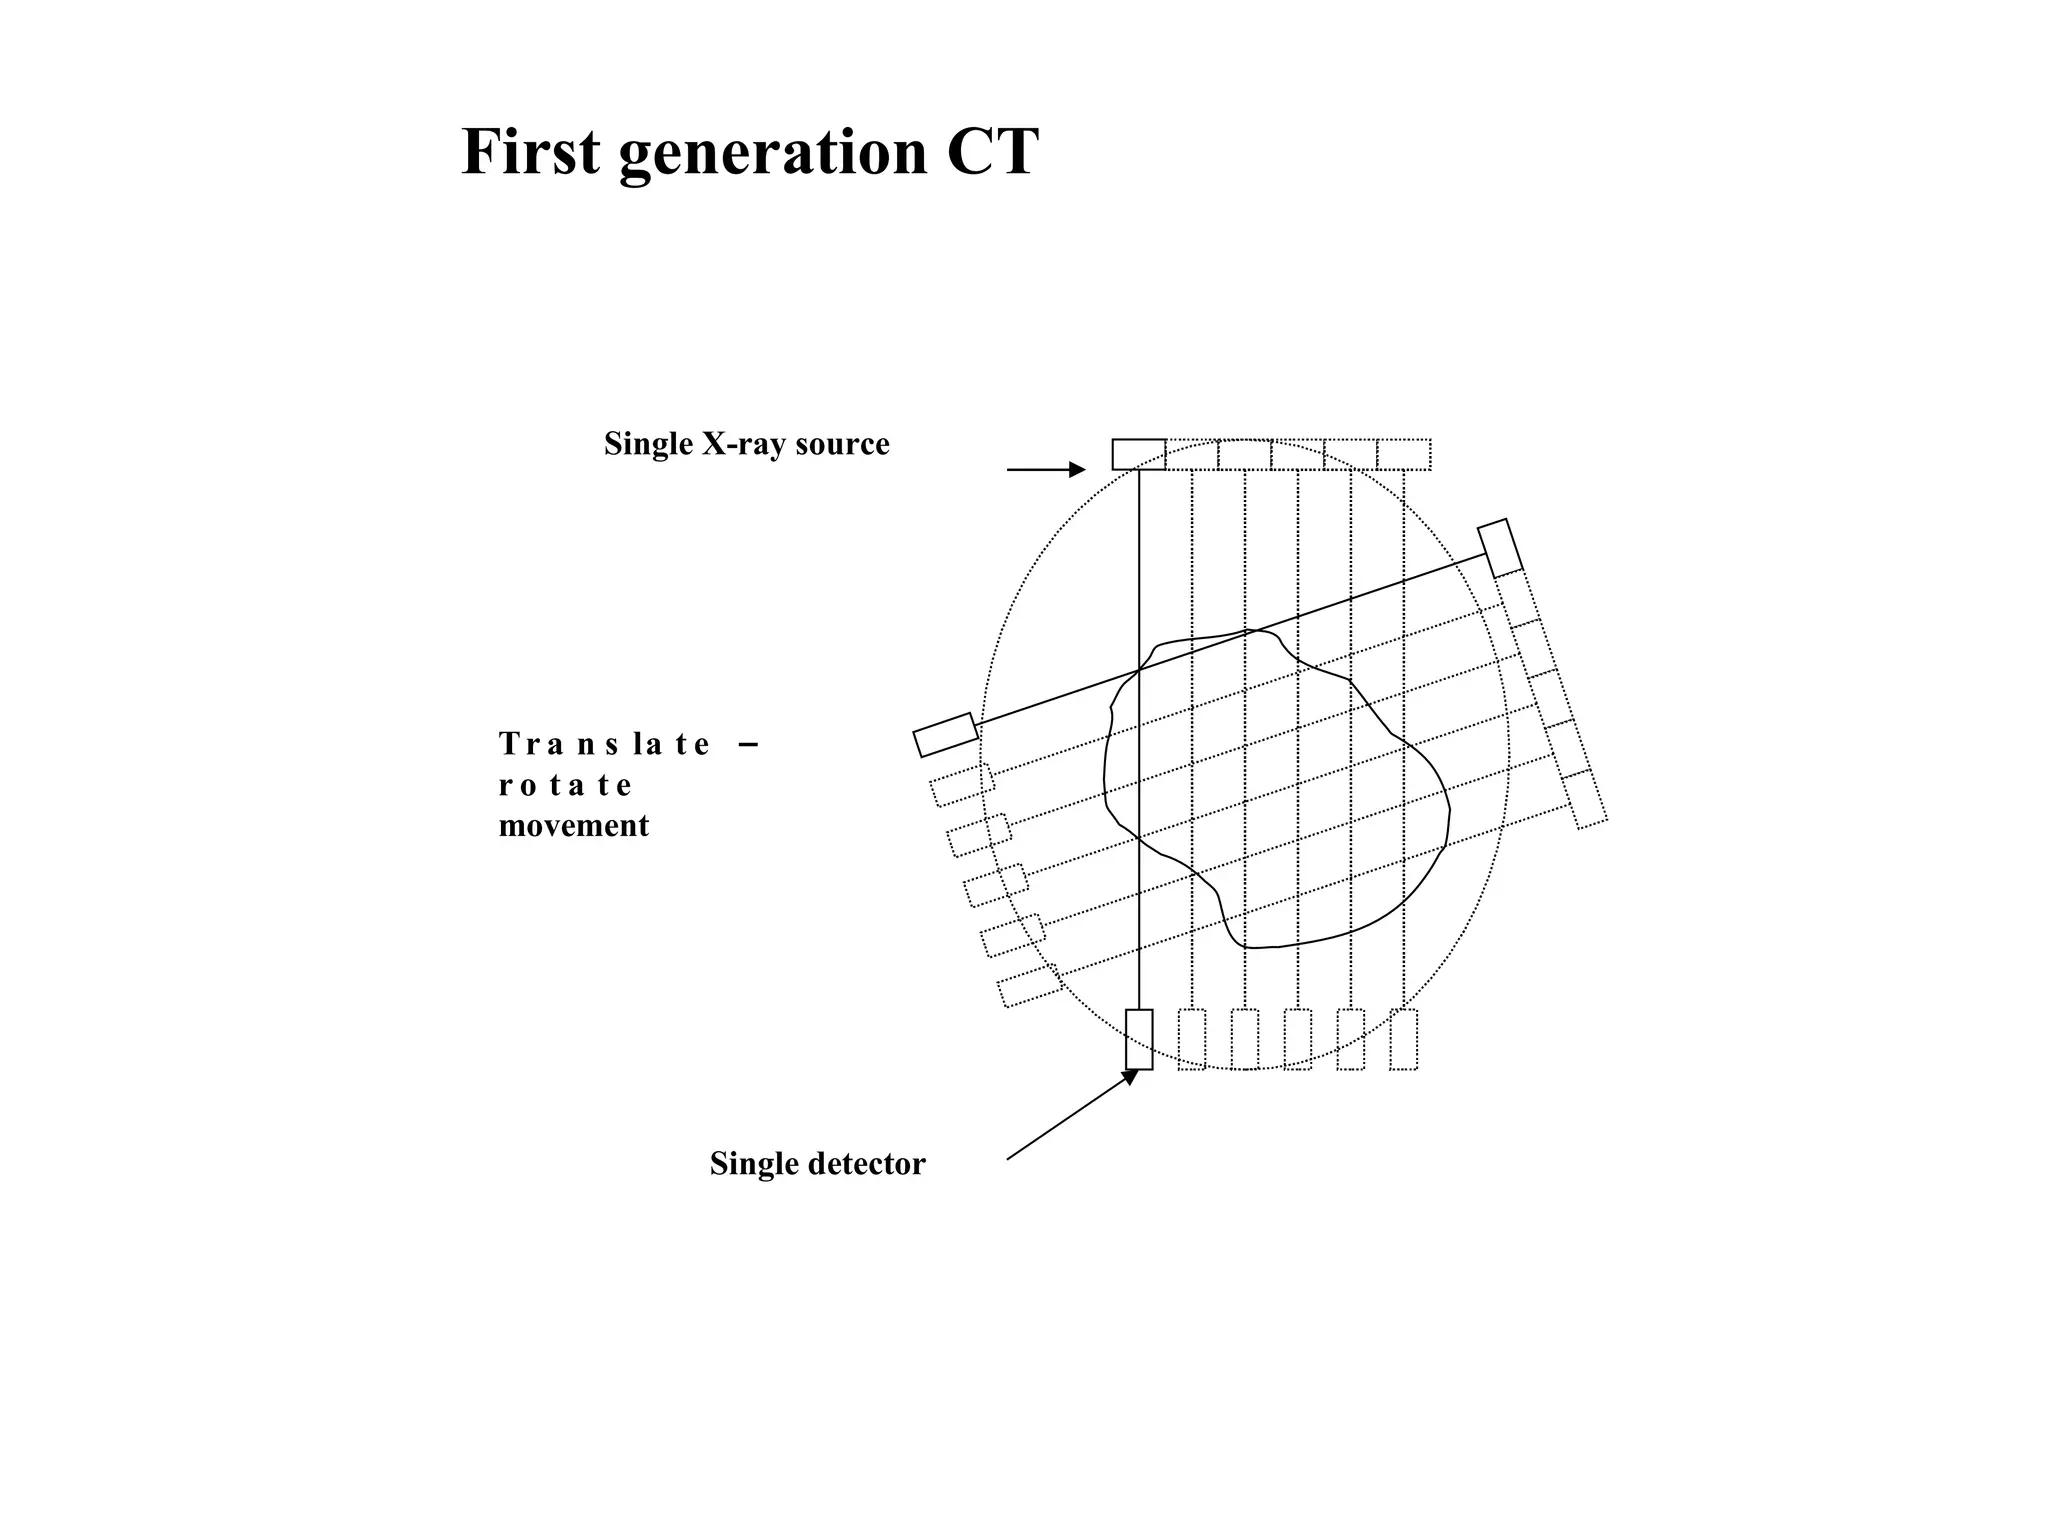

The document discusses various medical imaging modalities including x-rays, computed tomography (CT), and digital mammography. It describes the basic principles and historical development of these technologies, how images are formed, and what types of anatomical features and abnormalities they can detect. Key advances include the development of digital systems that allow image manipulation and remote consultation. While promising, digital mammography still faces challenges around resolution and cost.